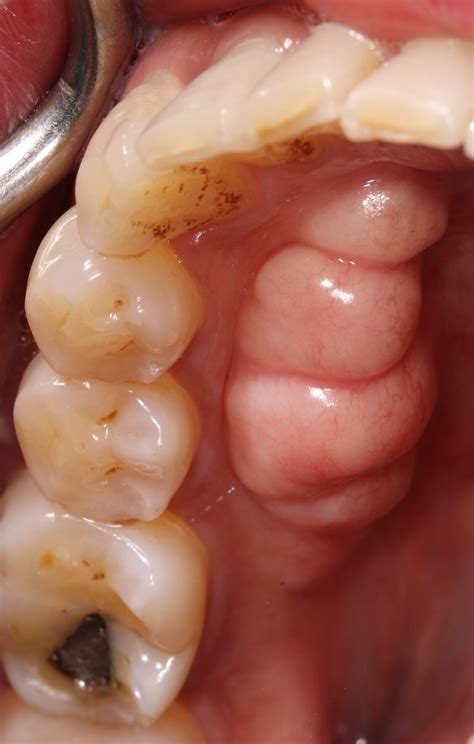

• Exostosis: These are bony projections that can occur on the jawbone, often near the molars.

• Visual Examination: The dentist will visually inspect the growth to determine its size, shape, and location.

• X-Rays: Dental X-rays may be taken to assess the extent of the growth and its impact on surrounding structures.

The treatment of bony growths on gums depends on their size, location, and impact on oral functions. In many cases, no treatment is necessary, and the growth can be monitored over time. However, if the growth causes discomfort or interferes with normal oral functions, treatment options may include:

• Surgical Removal: In cases where the growth is large or causes discomfort, surgical removal may be recommended. This procedure is typically performed under local anesthesia and involves the removal of the bony growth.